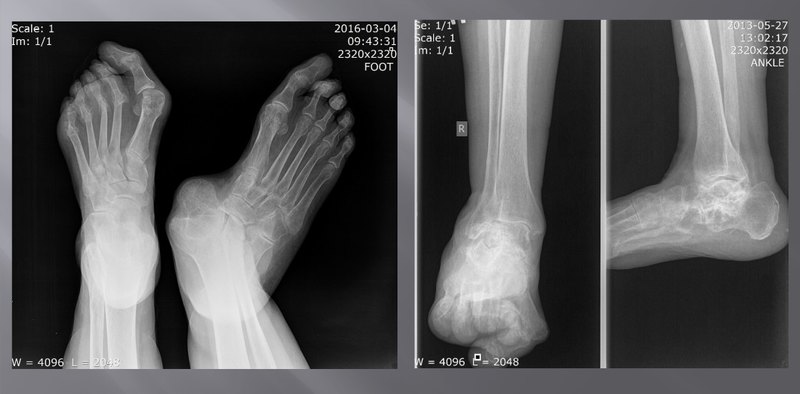

Но часто протезы необходимы тем, кто никогда не был на войне и даже не стал жертвой катастрофы. Иммунная система нашего организма — универсальный и сложный комплекс, благодаря которому мы остаемся невредимыми после регулярных контактов с окружающей средой. Однако иногда эта система оборачивается против своего хозяина: всему виной так называемые аутоиммунные заболевания, в результате которых иммунная система начинает воспринимать собственные ткани организма как чужеродные и атакует их. Подобные заболевания еще называют системными, поскольку, как правило, пораженными оказываются целые системы тела человека. Одно из следствий аутоиммунных заболеваний — сильные воспалительные реакции, в результате которых костная ткань небольших суставов попросту рассасывается и исчезает. Результатом даже незначительного изменения в структуре суставов может стать деформация всего скелета, возникающая по принципу цепной реакции. Из-за смещения осевых соотношений костей конечность деформируется и становится неспособна выполнять свои функции.

В наши дни самый простой способ исправить эту ситуацию — заменить поврежденный сустав или его части искусственным аналогом. Современные материалы, из которых изготавливаются эндопротезы, практически не взаимодействуют с внутренней средой организма и, как следствие, не отторгаются им. Часто ортопеды используют для подобных операций хорошо зарекомендовавший себя силикон. Однако у силиконовых протезов есть один существенный недостаток — они хрупкие, а потому выдерживают лишь небольшую нагрузку. Это заметно снижает силу хвата (если речь идет о суставах руки) и ограничивает использование конечности — в противном случае искусственный сустав разрушится и операцию придется проводить повторно. Кроме того, силикон не вступает в прочную связь с костью, а потому может попросту вылететь из гнезда. Но как быть в такой ситуации?

Специалисты из российского Центра хирургии стопы и кисти МЕДСИ бросили вызов этой проблеме. Протезирование — сложный и кропотливый процесс, и если необходимо заменить крупные суставы, то медики просто используют стандартные блоки. Однако подобная методика не подходит для мелких суставов кисти или стопы: строение каждого организма уникально, а потому не существует двух одинаковых рук или стоп. Кроме того, подобные операции требуют практически ювелирной работы. Выход был найден в технологии 3D-печати, которая подарила возможность находить индивидуальный подход к каждому пациенту. В современном мире трехмерная печать используется повсеместно, от космической промышленности до индустрии развлечений. Обычно трехмерные принтеры работают преимущественно с мягкими полимерами, однако в случае с суставами в дело пошел металл.

Шаг 1. Сначала пациент проходит через знакомую всему процедуру компьютерной томографии (КТ), которая регистрирует абсолютно все параметры его организма. После этого данные, полученные в результате сканирования, отправляются на производственный блок, не имеющий прямого отношения к клинике. Здесь информация превращается в компьютерную 3D-проекцию, на основе которой специалисты-биоинженеры формируют модель скелета. Ее конечности расположены так, чтобы соответствовать положению здоровых костей и суставов. Подобная методика сугубо индивидуальна, что позволяет избежать множества проблем еще до начала операции. Это очень важно: как уже было сказано, даже самый маленький сустав оказывает влияние на всю конечность в целом и незначительный дефект может стать причиной деформации всей кисти или стопы.